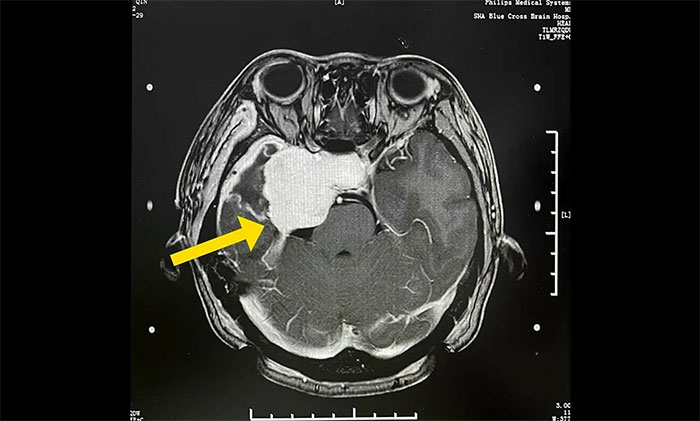

今年初医院收治了一位女性患者。该患者因突发视力模糊,头晕无法独立行走,在外院检查发现脑部右侧鞍旁肿块,手术病理诊断为海绵状血管瘤。

▲ 入院时MRI检查影像

肿瘤科(放疗)头部伽玛刀组陈琦主任完善检查并开展多学科评估讨论,其右侧鞍旁海绵状血管瘤与视神经等重要结构相邻,若不及时干预治疗,可因占位压迫进一步加重神经功能障碍,甚至导致失明。而该部位病灶的手术治疗难度高、风险大,术中可能对患者神经功能造成严重损害,应考虑采用创伤较小的伽玛刀治疗。